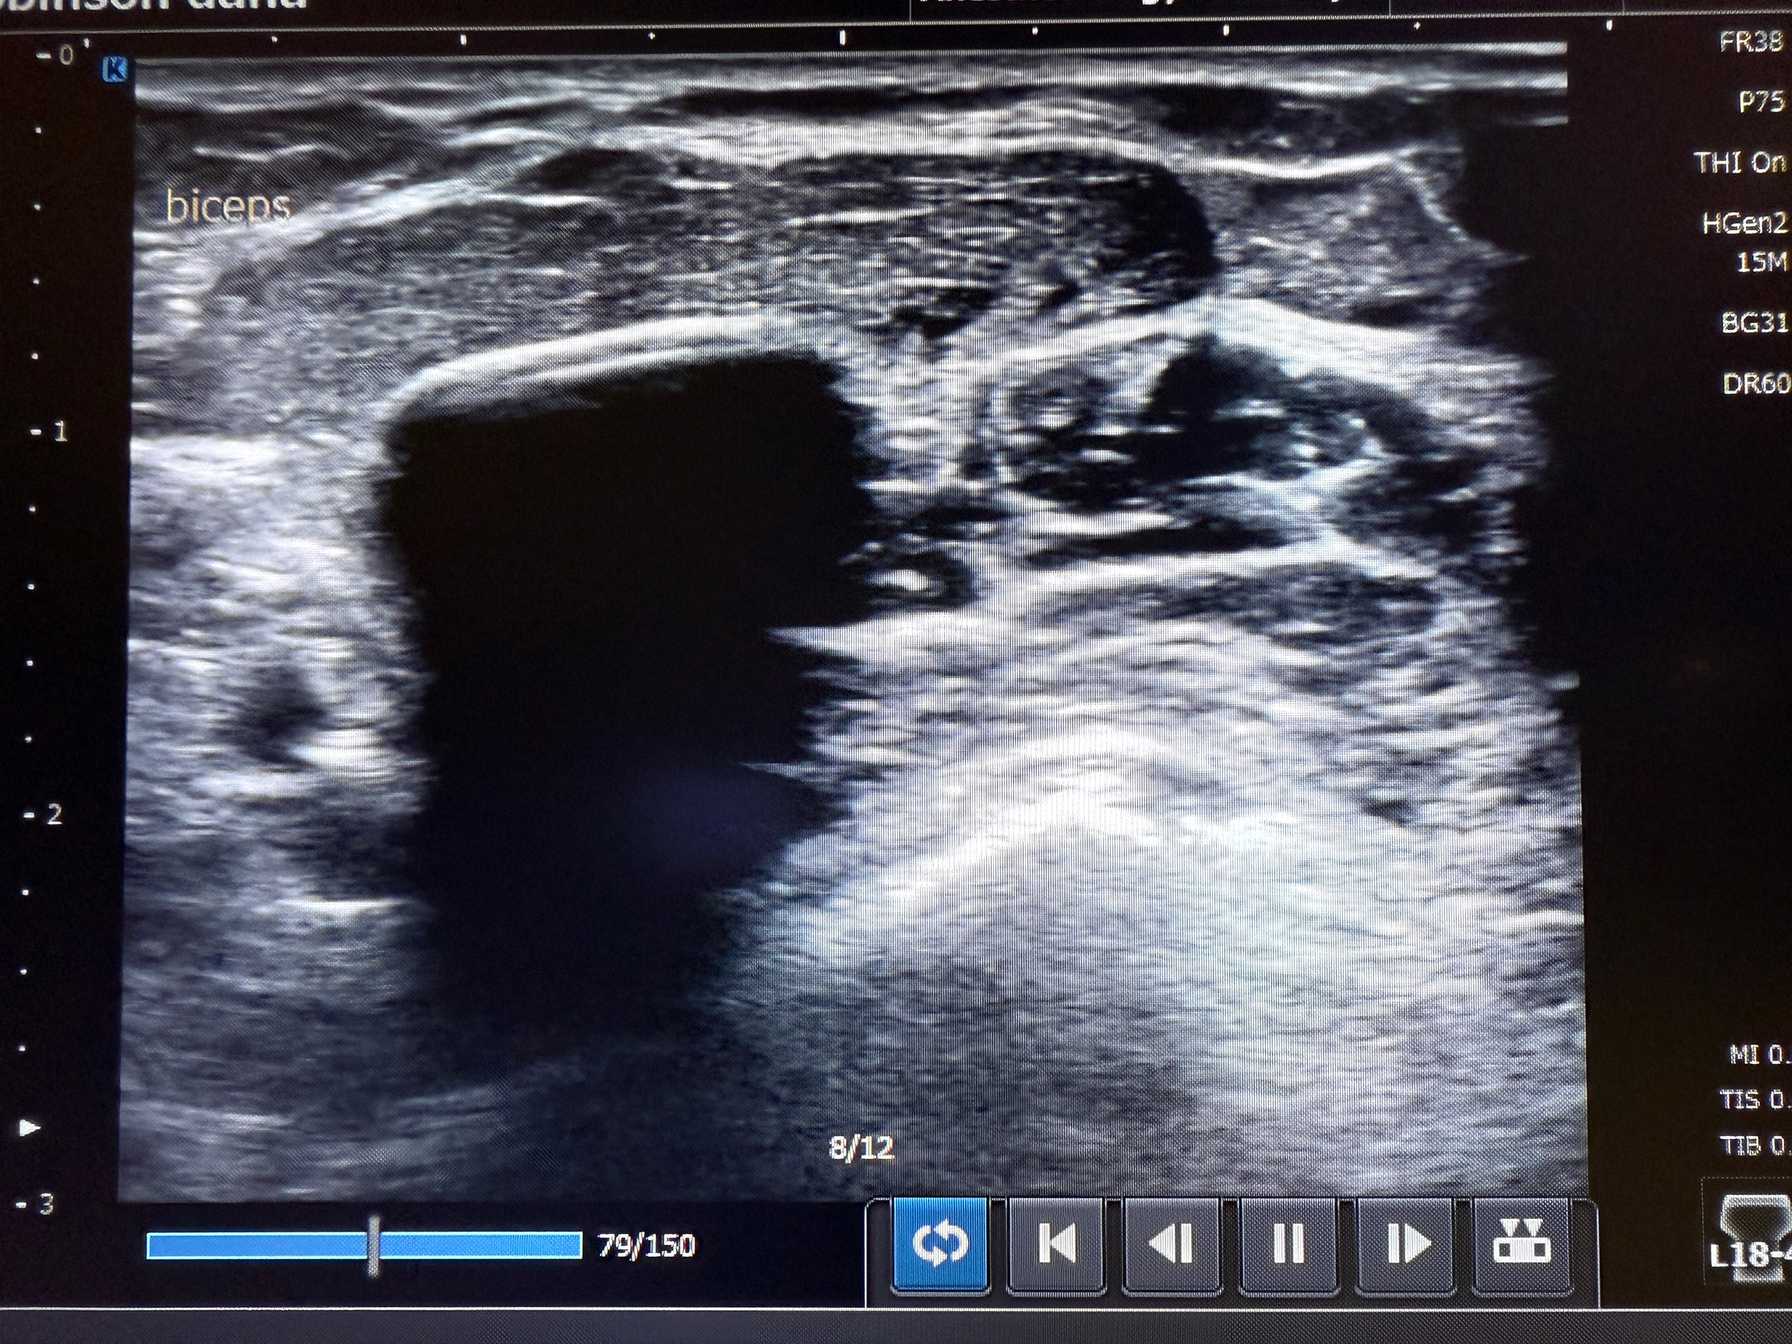

Advanced Diagnostics.

Innovative Interventions.